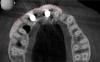

Tomographic images revealed a large tridimensional defect, with vertical and horizontal loss of bone extending to the apical third of teeth Nos. 6 and 8. Additionally, a buccal bone dehiscence was evident on tooth No. 5, and thin labial plates secondary to the orthodontic movement were present in several areas (Figure 3 and Figure 4).

Fig 3. Tomographic images revealed a tridimensional defect extending to the apical third of teeth Nos. 6 and 8, a buccal bone dehiscence on tooth No. 5, and associated thin labial plates.

Figure 3

Fig 4. Tomographic images revealed a tridimensional defect extending to the apical third of teeth Nos. 6 and 8, a buccal bone dehiscence on tooth No. 5, and associated thin labial plates.

Figure 4